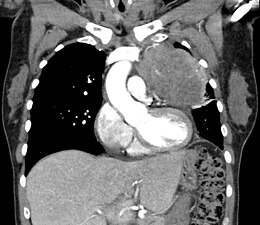

Le scanner thoracique est plus précis que la radiographie thoracique dans le diagnostic des thymomes, en raison d'une plus grande sensibilité envers les masses médiastinales. L'injection de produit de contraste iodé n'est pas forcément nécessaire, mais permet de préciser les rapports du thymome avec les structures vasculaires. Ceci permet à la fois la stadification et de préciser la stratégie chirurgicale lorsqu'elle est envisagée[28].

Les thymomes se présentent comme une masse bien définie du médiastin antérieur, proche du péricarde et dans un plan plus antérieur que les gros vaisseaux intrathoraciques (aorte ascendante et sa crosse, artère pulmonaire, veine cave supérieure). La masse peut être sphérique ou lobulée, mais présente un aspect homogène (plus rarement kystique) qui se réhausse après injection et peut contenir des calcifications[29].

Les critères scanographiques d'envahissement local doivent être recherchés car ils guideront le traitement. D'autre part, l'envahissement scanographique est corrélé au pronostic[30]. L'absence d'un liseré graisseux entre la masse et les vaisseaux, notamment l'aorte et la veine cave supérieure, est un signe d'envahissement local. L'ascension d'une coupole diaphragmatique, comme en radiographie thoracique, est un signe d'envahissement du nerf phrénique[31].

L'irrégularité des contours de la tumeur, ainsi que la présence de calcifications, de nécrose ou d'hémorragie intratumorale sont des signes de mauvais pronostic corrélés à des tumeurs plus agressives[32].